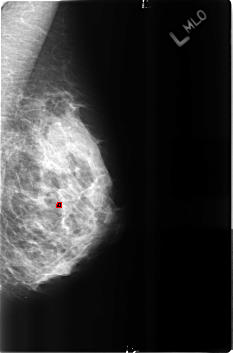

B_3162_1.LEFT_MLO

FILE: B_3162_1.LEFT_MLO.OVERLAY

TOTAL_ABNORMALITIES 1

ABNORMALITY 1

LESION_TYPE CALCIFICATION TYPE LUCENT_CENTERED DISTRIBUTION N/A

ASSESSMENT 2

SUBTLETY 4

PATHOLOGY BENIGN

TOTAL_OUTLINES 1

BOUNDARY